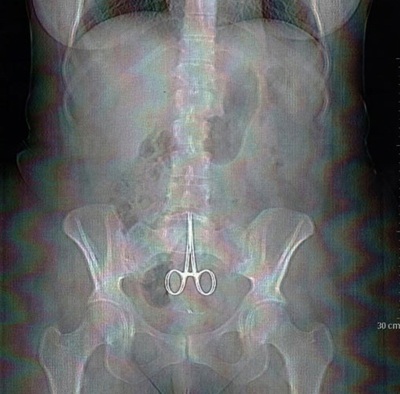

Ảnh chụp X-quang cho thấy chiếc kéo nằm trong bụng bệnh nhân.

Anne được đưa khẩn cấp tới bệnh viện, nơi kết quả chụp X-quang cho thấy một cái kéo phẫu thuật dài hơn 10cm nằm trong vùng bụng bệnh nhân.